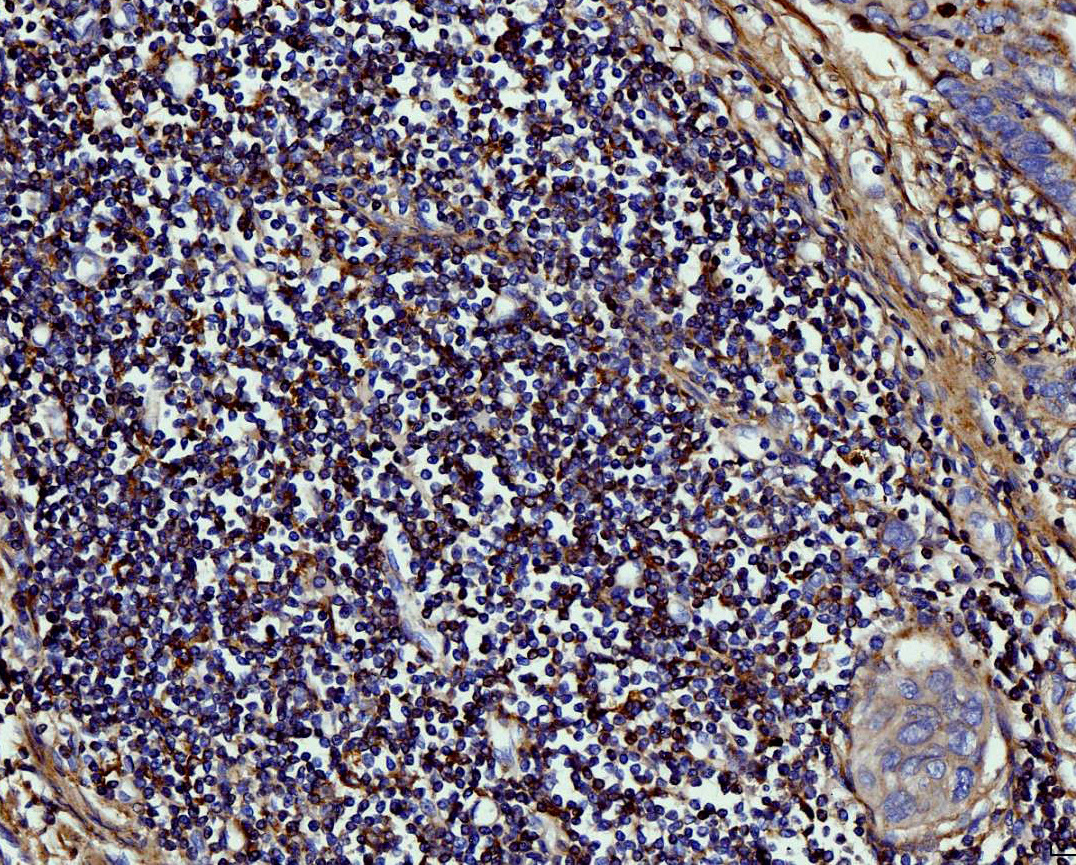

IHC analysis of MMP9 using anti-MMP9 antibody (PB0709).

MMP9 was detected in a paraffin-embedded section of human lymphadenoma tissue. Biotinylated goat anti-rabbit IgG was used as secondary antibody. The tissue section was incubated with rabbit anti-MMP9 Antibody (PB0709) at a dilution of 1:200 and developed using Strepavidin-Biotin-Complex (SABC) (Catalog # SA1022) with DAB (Catalog # AR1027) as the chromogen.